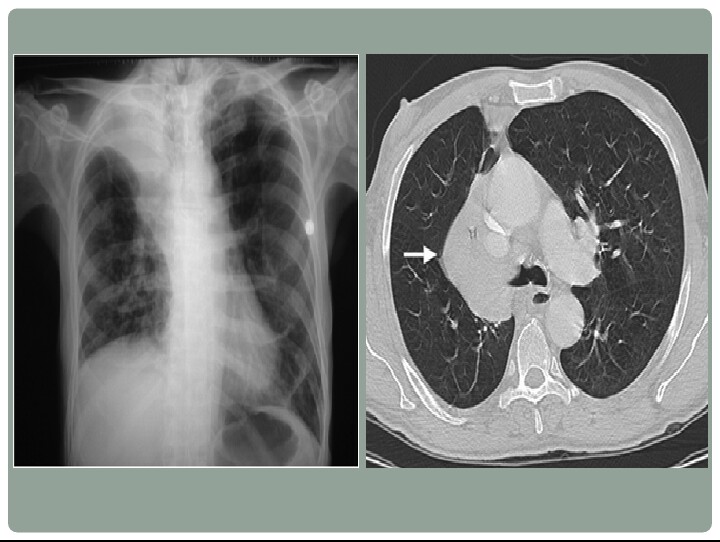

Golden S Sign